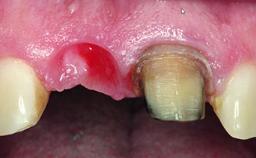

A 32-year-old female Caucasian patient with a compromised maxillary right central incisor was referred to us by a general dentist. Her chief complaints were discomfort and mobility of tooth 11 with unsatisfactory esthetics due to discoloration. The patient reported a previous trauma, some years earlier, as the origin of pathology on the afflicted tooth. Anamnesis was negative for any other dental or periodontal pathology in the remaining dentition. The patient did not take any medication and reported to be a light smoker (5–10 cigs/day). She had high esthetic expectations of her treatment. The extraoral examination revealed a high smile line with full exposure of her maxillary teeth and surrounding soft tissue in the area between the second premolars.